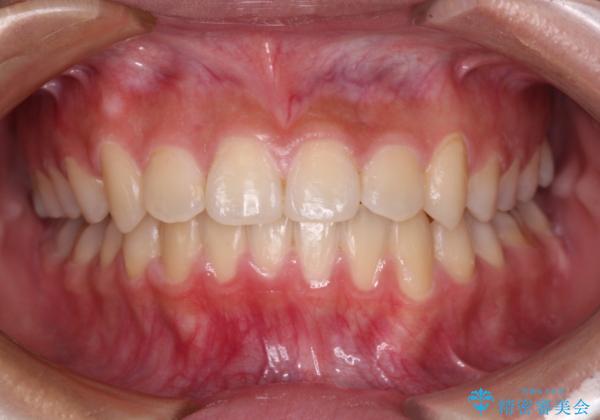

- 下顎の前突感と前歯の叢生を気にして来院された患者様です。

下顎前方位の骨格のため、下顎歯列に対して上顎歯列の幅が狭くなっていました。

急速拡大装置を用いて上顎骨を側方に拡大し、上顎の叢生を解消するとともに下顎歯列拡大により下顎の叢生も解消することとしました。

急速拡大装置使用直後は著しいスペースが正中に発現するため、ワイヤー矯正を行いますが、今回は治療期間を短くしたいとのことで、上下全体をワイヤー装置にて矯正治療することとしました。